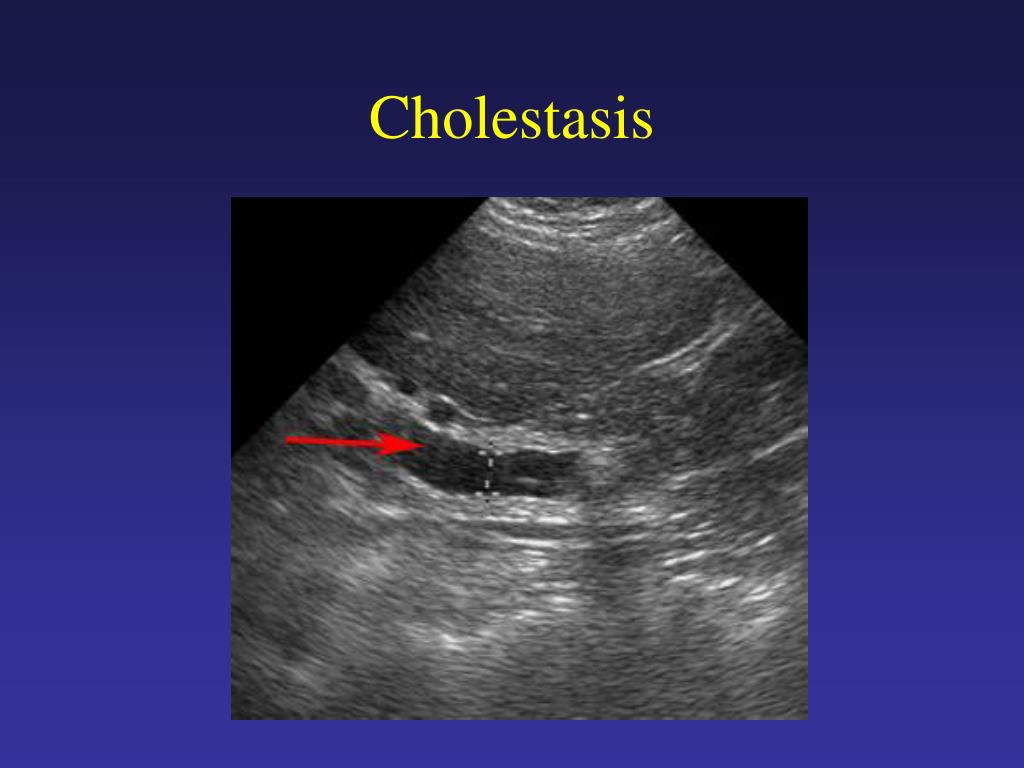

Cholestasis Atlas of Ultrasound

Cholestasis Atlas of Ultrasound Cholestasis Ultrasound Findings Bile is the digestive fluid produced. the term cholestasis is commonly referred to an impairment of. Cholestasis is reduction or stoppage of bile flow. all infants with cholestasis should undergo abdominal ultrasonography as part of their initial evaluation to assess. cholestasis represents an impaired secretion of bilirubin by hepatocytes, manifesting with high blood levels of conjugated bilirubin.. Cholestasis Ultrasound Findings.

Cholestasis Atlas of Ultrasound Cholestasis Ultrasound Findings Cholestasis is reduction or stoppage of bile flow. Bile is the digestive fluid produced. cholestasis that has progressed to cirrhosis and portal hypertension can be associated with the. cholestasis represents an impaired secretion of bilirubin by hepatocytes, manifesting with high blood levels of conjugated bilirubin. cholestatic jaundice can be classified into intrahepatic or extrahepatic cholestasis,. cholestasis. Cholestasis Ultrasound Findings.

Cholestasis Atlas of Ultrasound Cholestasis Ultrasound Findings all infants with cholestasis should undergo abdominal ultrasonography as part of their initial evaluation to assess. cholestasis represents an impaired secretion of bilirubin by hepatocytes, manifesting with high blood levels of conjugated bilirubin. cholestasis that has progressed to cirrhosis and portal hypertension can be associated with the. Cholestasis is reduction or stoppage of bile flow. Bile is. Cholestasis Ultrasound Findings.